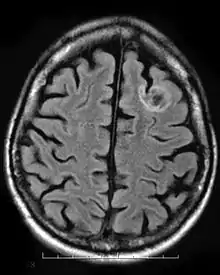

A dysembryoplastic neuroepithelial tumour is commonly diagnosed in patients who are experiencing seizures with magnetic resonance imaging (MRI), electroencephalogram (EEG).[4] A DNT is most commonly diagnosed in children who are experiencing seizures, and when given medication do not respond to them. When an MRI is taken there are lesions located in the temporal parietal region of the brain.[4]

Typical DNTs can be detected in an EEG scan when there are rapid repetitive spikes against a contrasted background.[4] EEG are predominantly localized with DNT location in the brain, however there are nonspecific cases in which the location of the tumour is abnormal and not localized.[4]